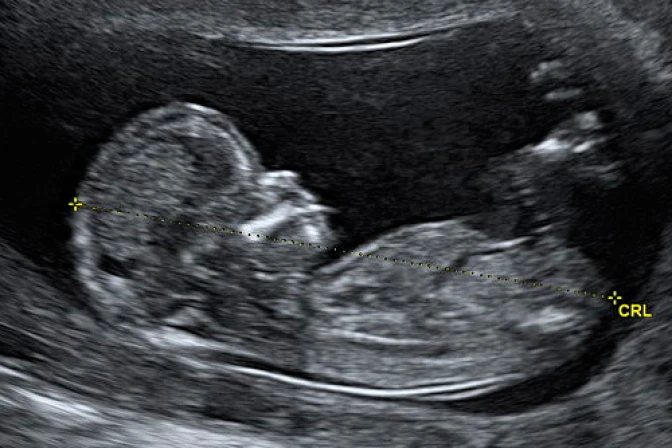

A mediados de 2012, Esteffany Quintana, de 28 años, perdió a una de las gemelas que llevaba en el vientre, y una vez alcanzados los 8 meses y medio de gestación fue sometida a una cesárea. Desde entonces exige a las autoridades médicas del seguro social peruano, Essalud, que le devuelvan el cuerpo de la bebé fallecida para darle cristiana sepultura.

La joven peruana dio a luz el 29 de agosto de 2012 a una de las gemelas, Gabriela, mientras que los médicos del Hospital Rebagliati extrajeron el cuerpo sin vida de la otra bebé, a quien su madre llamó Isabela.

En un comunicado, las autoridades médicas señalaron que Isabella falleció "a las 13 o 14 semanas con un peso de 180 gramos, que no es considerado según la normativa institucional como muerte fetal o perinatal, porque para ello tendría que haber tenido 22 semanas y pesar igual o mayor de 500 gramos".